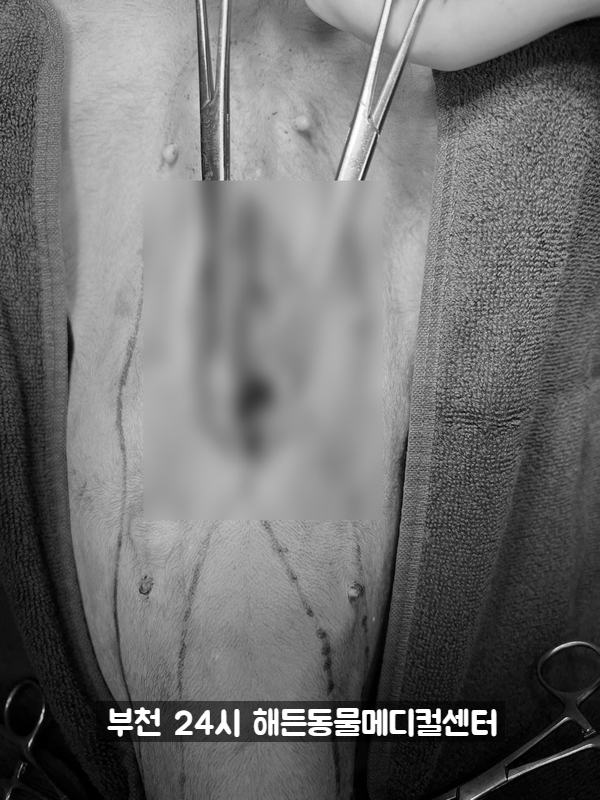

수술이 잘 됐어요.

자궁축농증 유선종양 전체 적출종양 등 3개의 큰 수술을 모두 끝냈습니다.